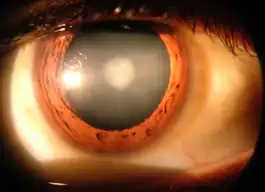

Best's vitelliform macular dystrophy (BVMD) is one of the most common Best1-associated diseases. BVMD typically becomes noticeable in children and is represented by the buildup of lipofuscin (lipid residuals) lesions in the eye.[6][10] Diagnosis normally follows an abnormal electrooculogram in which decreased activation of calcium channels in the basolateral membrane of the retinal pigment epithelium becomes apparent. A mutation in the BEST1 gene leads to a loss of channel function and eventually retinal degeneration.[10] Although BVMD is an autosomal dominant form of macular dystrophy, expressivity varies within and between affected families although the overwhelming majority of affected families come from northern European descent.[7][10] Typically, people with this condition experience five progressively worsening stages, though timing and severity varies greatly. BVMD is often caused by the single missense mutations; however, amino acid deletions have also been identified.[7] A loss of function of the Best1 chloride channel could likely explain some of the most common issues associated with BVMD: an inability to regulate intracellular ion concentrations and regulate overall cell volume.[13] To date, over 100 disease-causing mutations have been related to BVMD as well as a number of other degenerative retinal diseases.[12]

Autosomal dominant vitreoretinochoroidopathy was first identified in 1982 and presents itself in both eyes with decreases in peripheral vision due to excessive fluid and changes in eye retinal pigmentation. Early onset cataracts are also likely.[7]